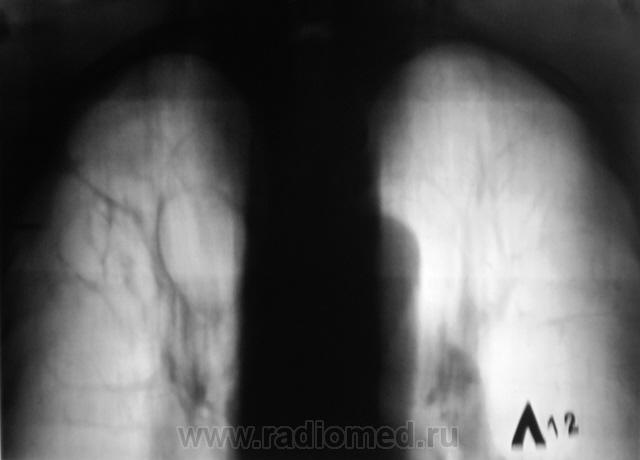

Контроль после флюорографии.

Произведено стандартное дообследование.

Процесс свежий. Но, вот кисты справа в верхней доле были, и ранее.